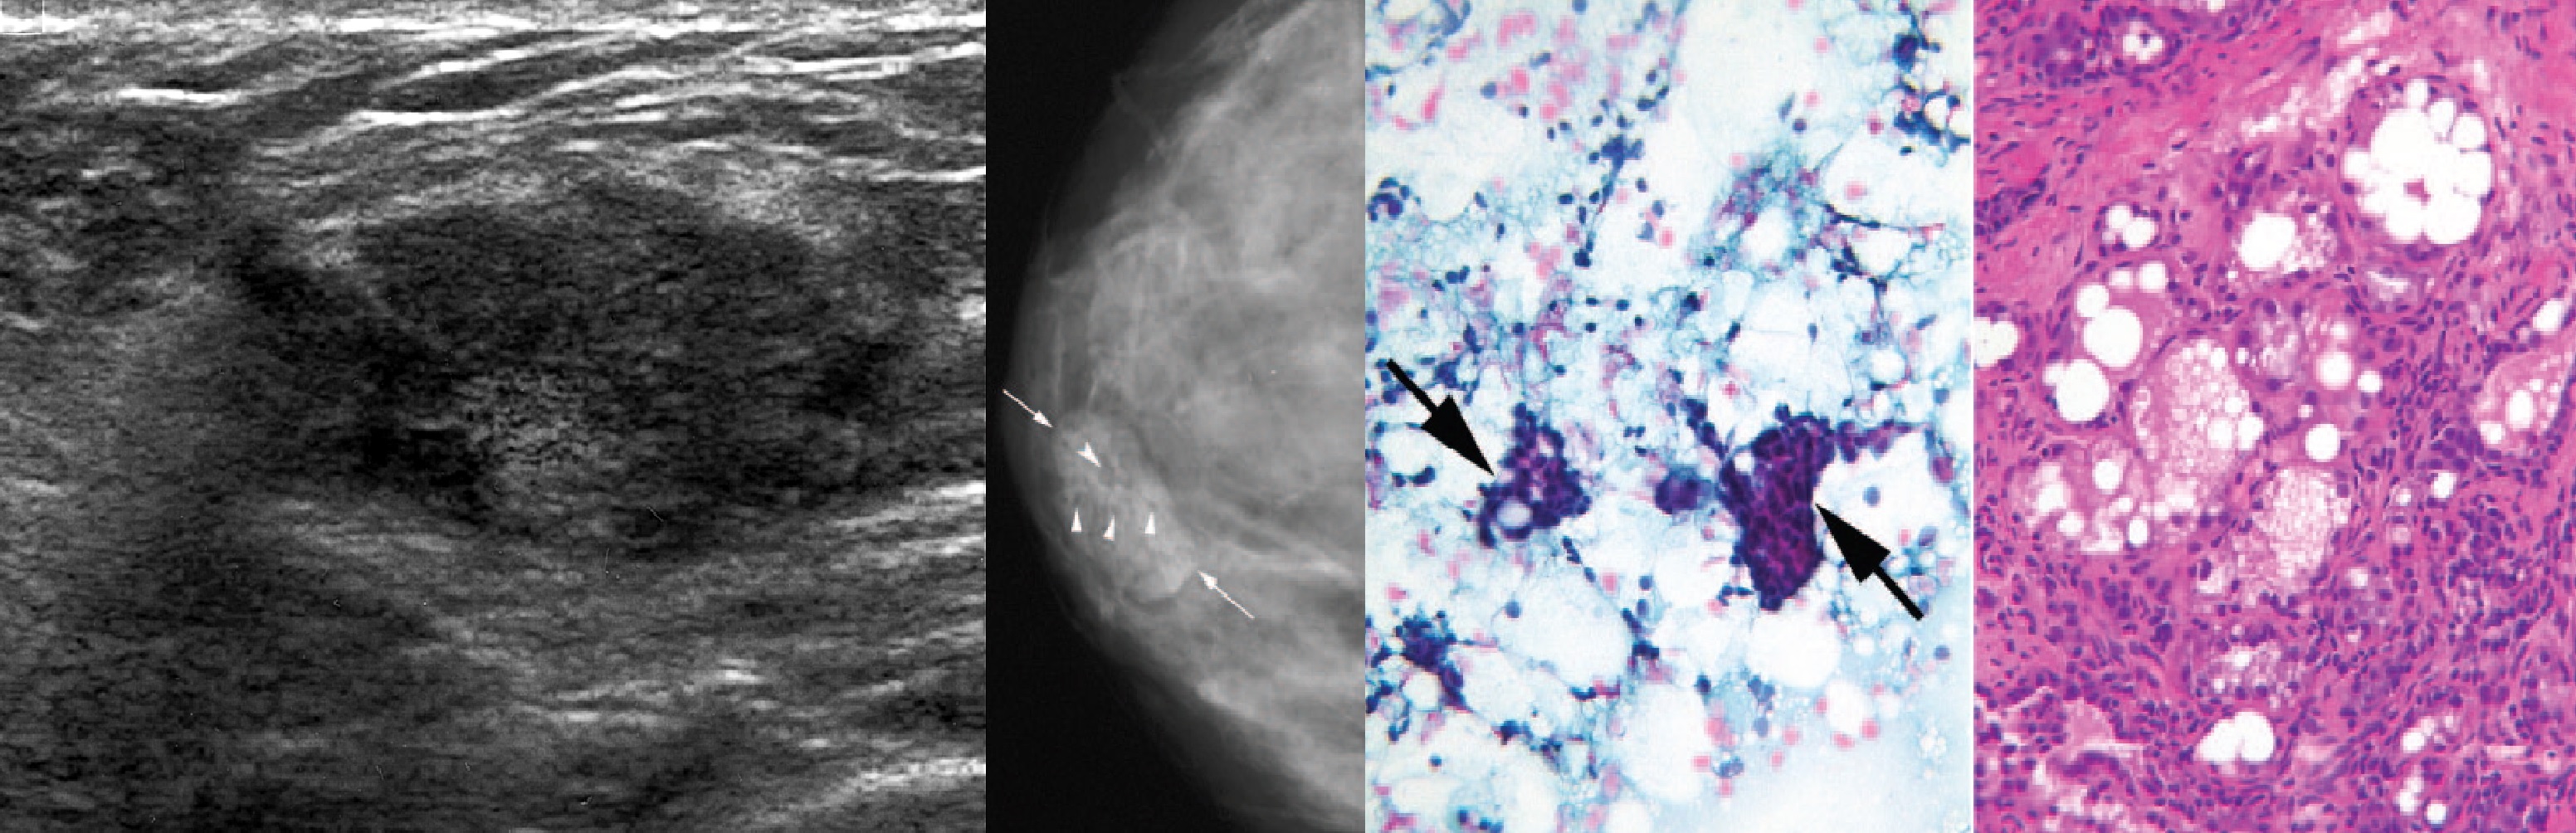

Микрогландулярный аденоз

Фиброаденома молочной железы - доброкачественное образование, которое часто встречается у женщин. Оно может быть обнаружено при помощи различных методов диагностики, включая маммографию. Ниже представлены фотографии, помогающие понять, как выглядит данное заболевание.

Маммография и ее роль в диагностике фиброаденомы молочной железы

Маммография - это рентгенологическое исследование молочных желез. Оно позволяет выявить различные изменения в тканях, включая фиброаденому. На маммограммах можно увидеть структурные особенности опухоли и отследить ее динамику во времени.